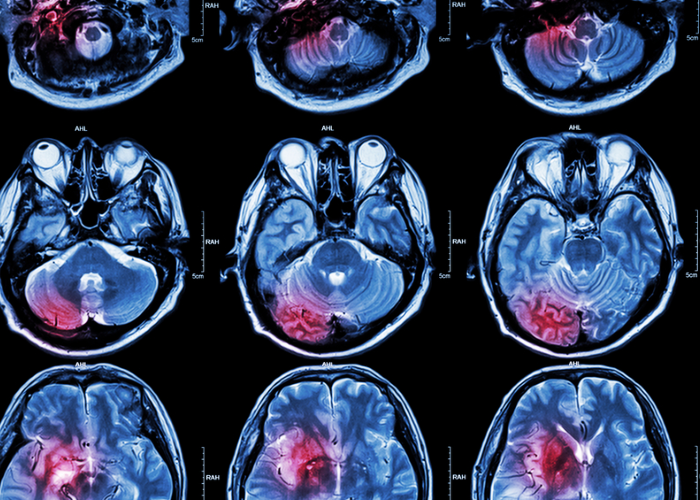

In MS the immune system damages cells in the central nervous system (the brain, spinal cord or optic